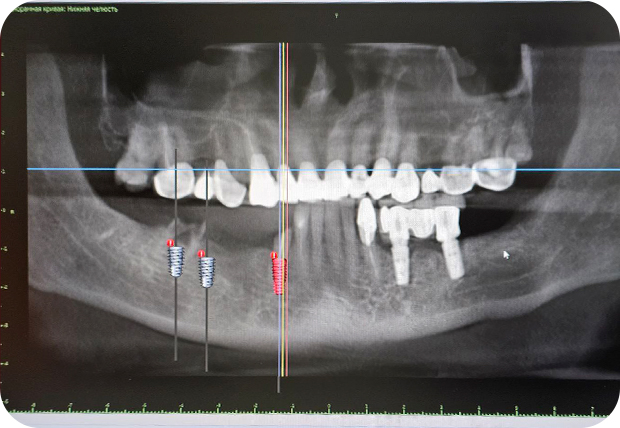

Приходите после удаления на консультацию обязательно с КТ обеих челюстей